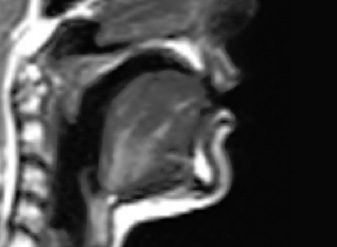

The tongue is a large flexible muscular organ that stretches from its root at the top of the throat to its tip, which can be protruded from the mouth. Most of the tongue’s mass is hidden from view, inside of the oral and pharyngeal cavities. The tongue is crucial to speech production: a large number of consonant and all vowel sounds are produced by modifying the shape of the tongue. Consonantal sounds are often produced by using the tongue to block or restrict air flow in the oral tract, while vowel sounds and sonorous consonants such as [j], [l], [ɹ] and [w] are produced by shaping pockets of air inside of the vocal tract so that these pockets of air resonate at specific frequency ranges.

Figure 1: A midsagittal MRI image of the vocal tract